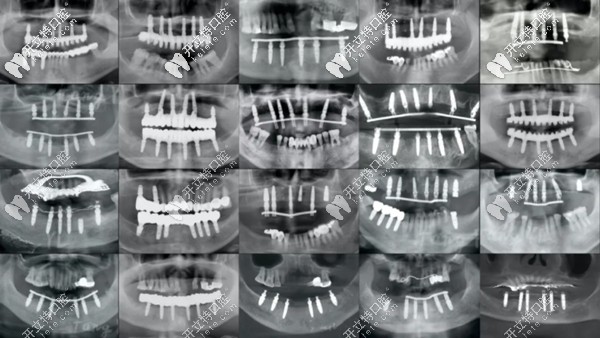

各類(lèi)全口種植牙的全景片展示圖

(各類(lèi)全口種植牙的全景片展示圖)

這么說(shuō)吧,從上圖可以看出,即便同樣是全口種植牙,同樣是上下6顆種植體,同樣采用all-on-6即刻種植技術(shù),但用的植體長(zhǎng)短、粗細(xì)不等。

其實(shí)它們也代表了不同品牌、規(guī)格、型號(hào)的植體,所以,價(jià)位也是不能一概而論的。